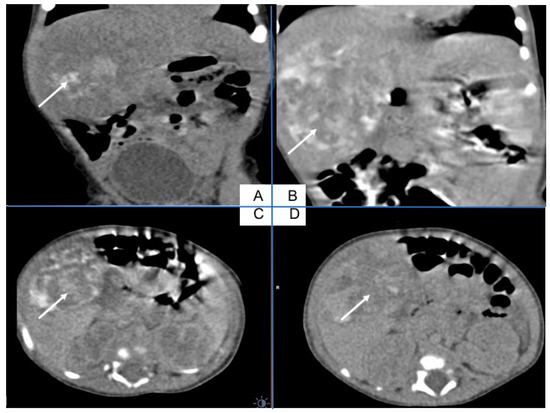

An abdominal nonenhanced (A) and enhanced arterial phase (B) coronal view, arterial phase (C) and portal phase (D) axial view indicate on the hepatic mass with bleeding (A), and central necrosis (Figure 2). After gadolinium contrast injection, there is poor peripheral enhancement in the arterioportal phase (C) and in the late portal venous phase, the CT image shows poor hypodense lesions (D) (Figure 2).

Figure 2. Abdominal CT with liver tumor in the right lobe. An abdominal nonenhanced (A) and enhanced arterial phase (B) coronal view, arterial phase (C) and portal phase (D) axial view indicate on the hepatic mass with bleeding (A), and central necrosis. After gadolinium contrast injection, there is poor peripheral enhancement in the arterioportal phase (C) and in the late portal venous phase CT image shows poor hypodense lesions (D).